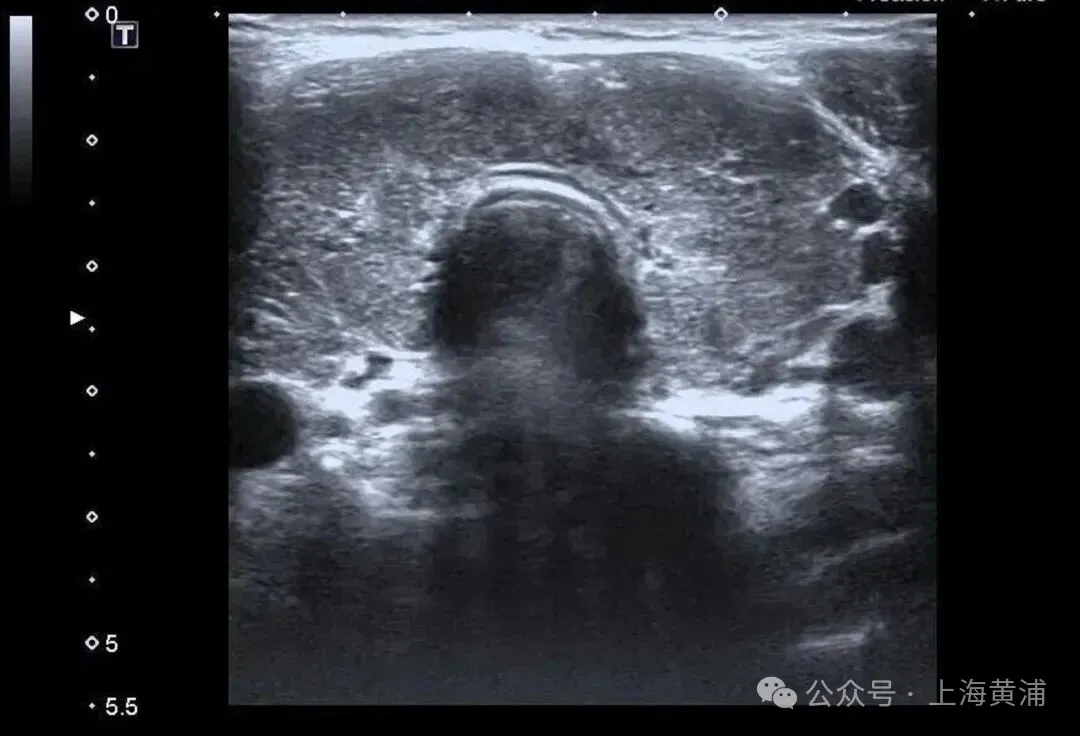

住院后的检查闭幕泄露

陈女士的体魄

正被一场“激素风暴”席卷

甲状腺功能检查中,游离T3高达20.83 pmol/L(平方值3.5 - 6.5pmol/L),游离T4高达88.42 pmol/L(平方值11.5 - 22.7pmol/L),这两项中枢激素齐逾越平方上限数倍,而本应调控它们的促甲状腺激素(TSH)却险些测不出来,这明确阐明了陈女士患有极其严重的甲状腺毒症。腹黑超声闭幕相同辞谢乐不雅,射血分数仅有40%(平方应高于55%),这意味着腹黑泵血才略大幅下跌。